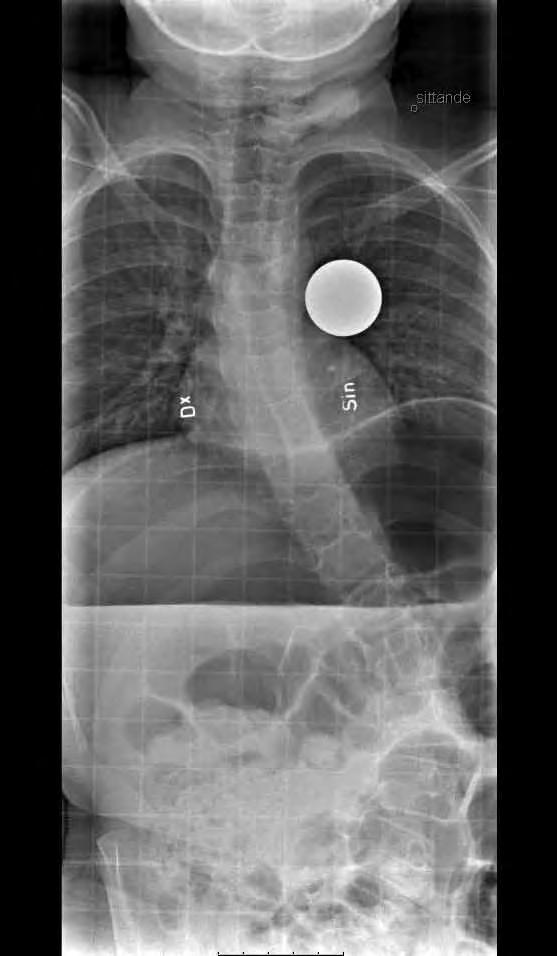

11-årig flicka med CP och spastisk tetrapares. Hon hade en extremt snabb skoliosutveckling från Cobb 45 grader till drygt 70 grader på tre månader. detta föranledde en snar op från Th2 till L5 med transpedikulära skruvar enl. Suk. Blödningen uppgick till 1500 ml. Postoperativt har vi inga restriktioner avseende mobiliseringen då så många fixationspunkter användes. Patienten hade postoperativt lunginflammation som dock snabbt svarade på antibiotikabehandling.

Preop PA sittande visar en 65-gradig skolios enligt Cobb.